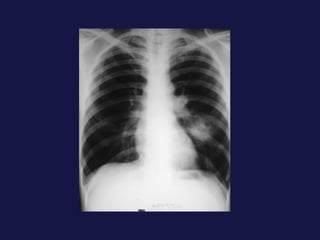

Carcinoma epidermoide ( 30% ). Bronquios centrales, ayuda la citología de esputo. Localización central. Provoca obstrucción bronquial con atelectasia o neumonía postobstructiva sin perdida de volumen mucha cavitación con paredes gruesas e irregulares. 40% lesión periférica,   con bordes espiculados o lobulados. Causa frecuente de pancoast-Tobías.

Tumor central. 60-75% próximos a los hilios. Epidermoides y células pequeñas. Agrandamiento asimétrico del hilio o masa de bordes espiculados. Atelectasia lobular, segmentaria o de todo el pulmón. Sobreinfección del parénquima distal y neumonía postobstructiva, a menudo abscesificada.

Carcinoma epidermoide (30% ). Bronquios centrales, ayuda la citología de esputo. Localización central. Provoca obstrucción bronquial con atelectasia o neumonía postobstructiva sin perdida de volumen mucha cavitación con paredes gruesas e irregulares. 40% lesión periférica, con bordes espiculados o lobulados. Causa frecuente de pancoast-Tobías.

Tumor central. 60-75%próximos a los hilios. Epidermoides y células pequeñas. Agrandamiento asimétrico del hilio o masa de bordes espiculados. Atelectasia lobular, segmentaria o de todo el pulmón. Sobreinfección del parénquima distal y neumonía postobstructiva, a menudo abscesificada.